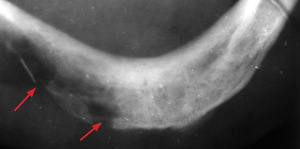

Metodą z wyboru jest leczenie chirurgiczne, w razie wskazań skojarzone z uzupełniającym napromienianiem. U chorych będących na granicy operacyjności zabieg może być poprzedzony chemioterapią neoadjuwantową. Alternatywą dla leczenia chirurgicznego jest radioterapia. U osób leczonych z powodu raka wargi dolnej za pomocą brachyterapii lub teleradioterapii nie ma możliwości oceny mikroskopowej radykalności leczenia. W 7-10 proc. przypadków powstają po leczeniu ubytki czerwieni wargowej oraz martwica popromienna żuchwy (osteoradionecrosis mandibulae), chociaż dzięki zastosowaniu nowej techniki naświetlań IMRT (tzw. dose painting) odsetek ten się sukcesywnie obniża. Na ryc. 3

przedstawiono zdjęcie zgryzowe żuchwy, na którym strzałkami zaznaczono obszar popromiennej martwicy kości. Stała utrata śliny, związana z niedomy kalnością szpary ustnej, może być przyczyną dysjonii, stanowiącej zagrożenie ciężkimi zaburzeniami rytmu serca. U chorych w młodym wieku wzrasta 275-krotnie ryzyko powstania po 20-25 latach wtórnych nowotworów popromiennych.